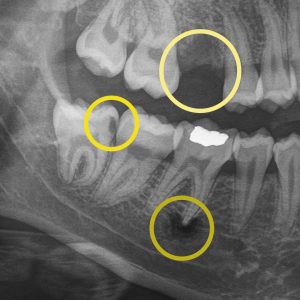

Digital Dental X-Rays: What They Tell Us About Your Smile and Oral Health

Digital X-rays help your dentist detect concerns early, track changes over time, and personalize your care…